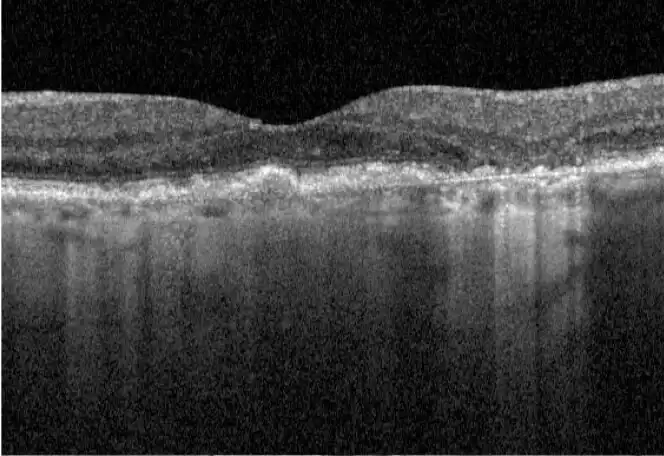

Neovascular AMD

- In clinical trials, use of IZERVAY was associated with increased rates of neovascular (wet) AMD or choroidal neovascularization (7% when administered monthly and 4% in the sham group) by Month 12. Over 24 months, the rate of neovascular (wet) AMD or choroidal neovascularization in the GATHER2 trial was 12% in the IZERVAY group and 9% in the sham group. Patients receiving IZERVAY should be monitored for signs of neovascular AMD.